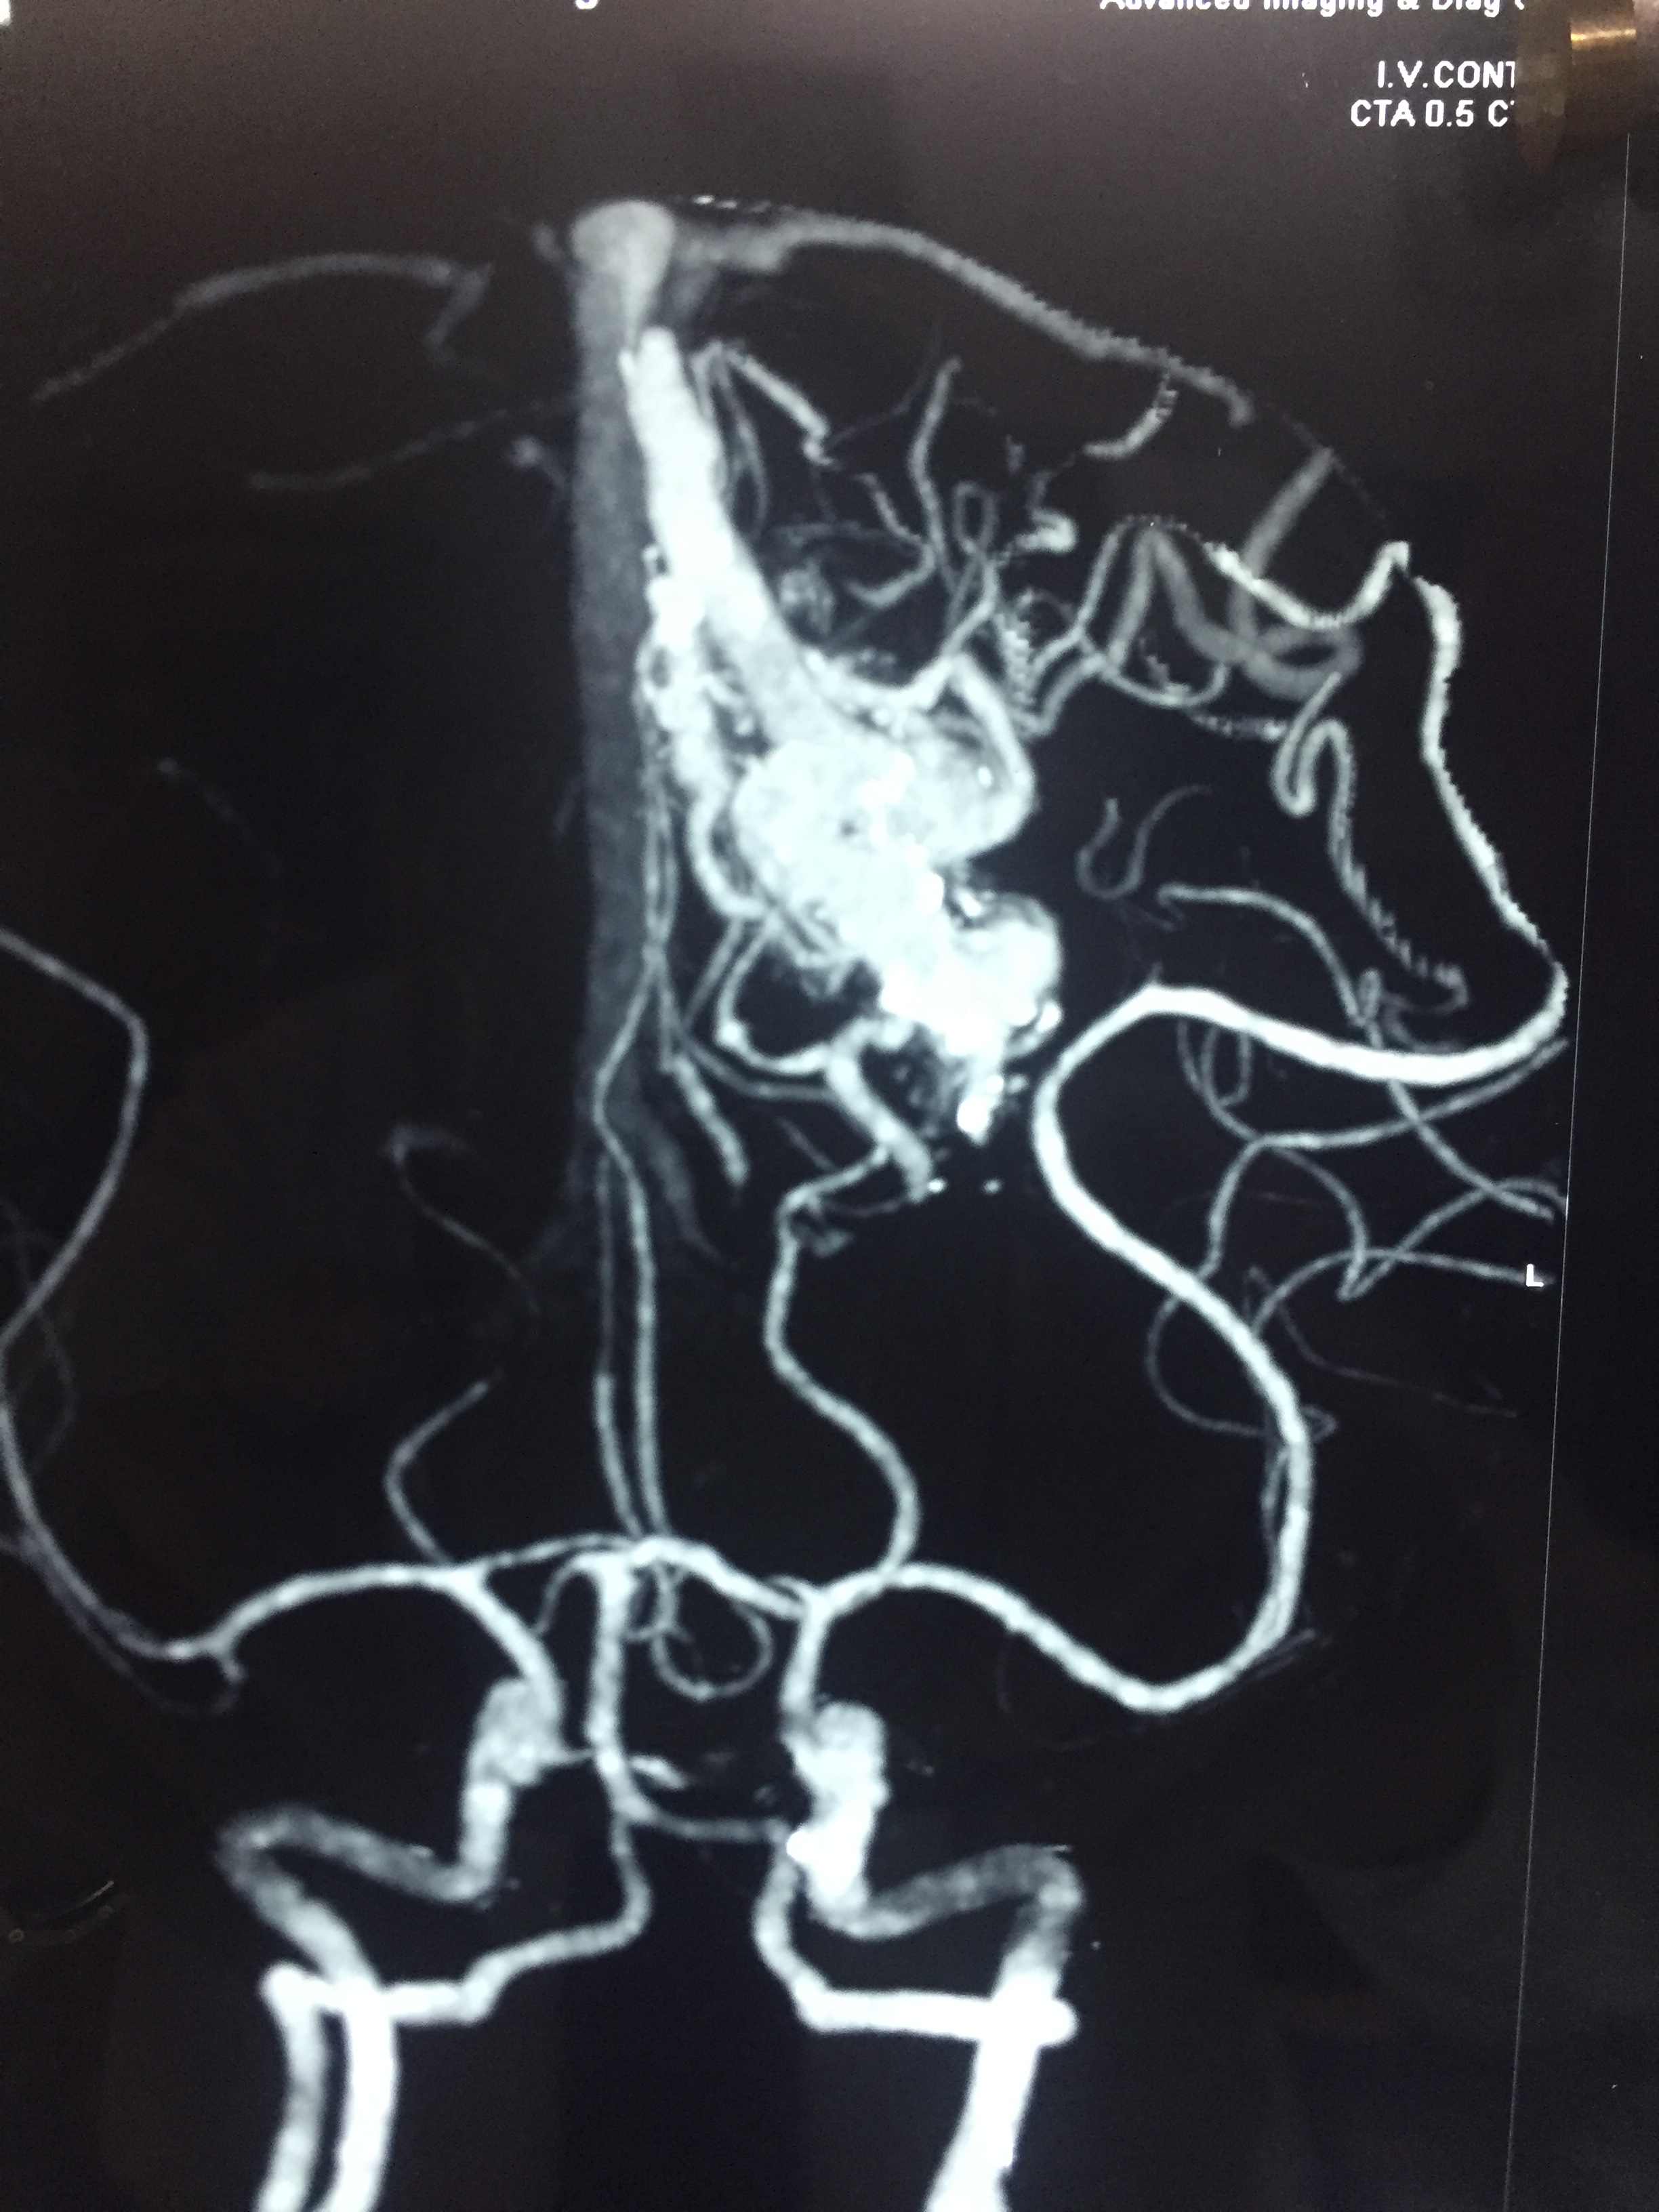

Lt. Occipital AVM : Surgery - Microsurgical excision of AVM (Lt. Occipital Grade IV AVM)